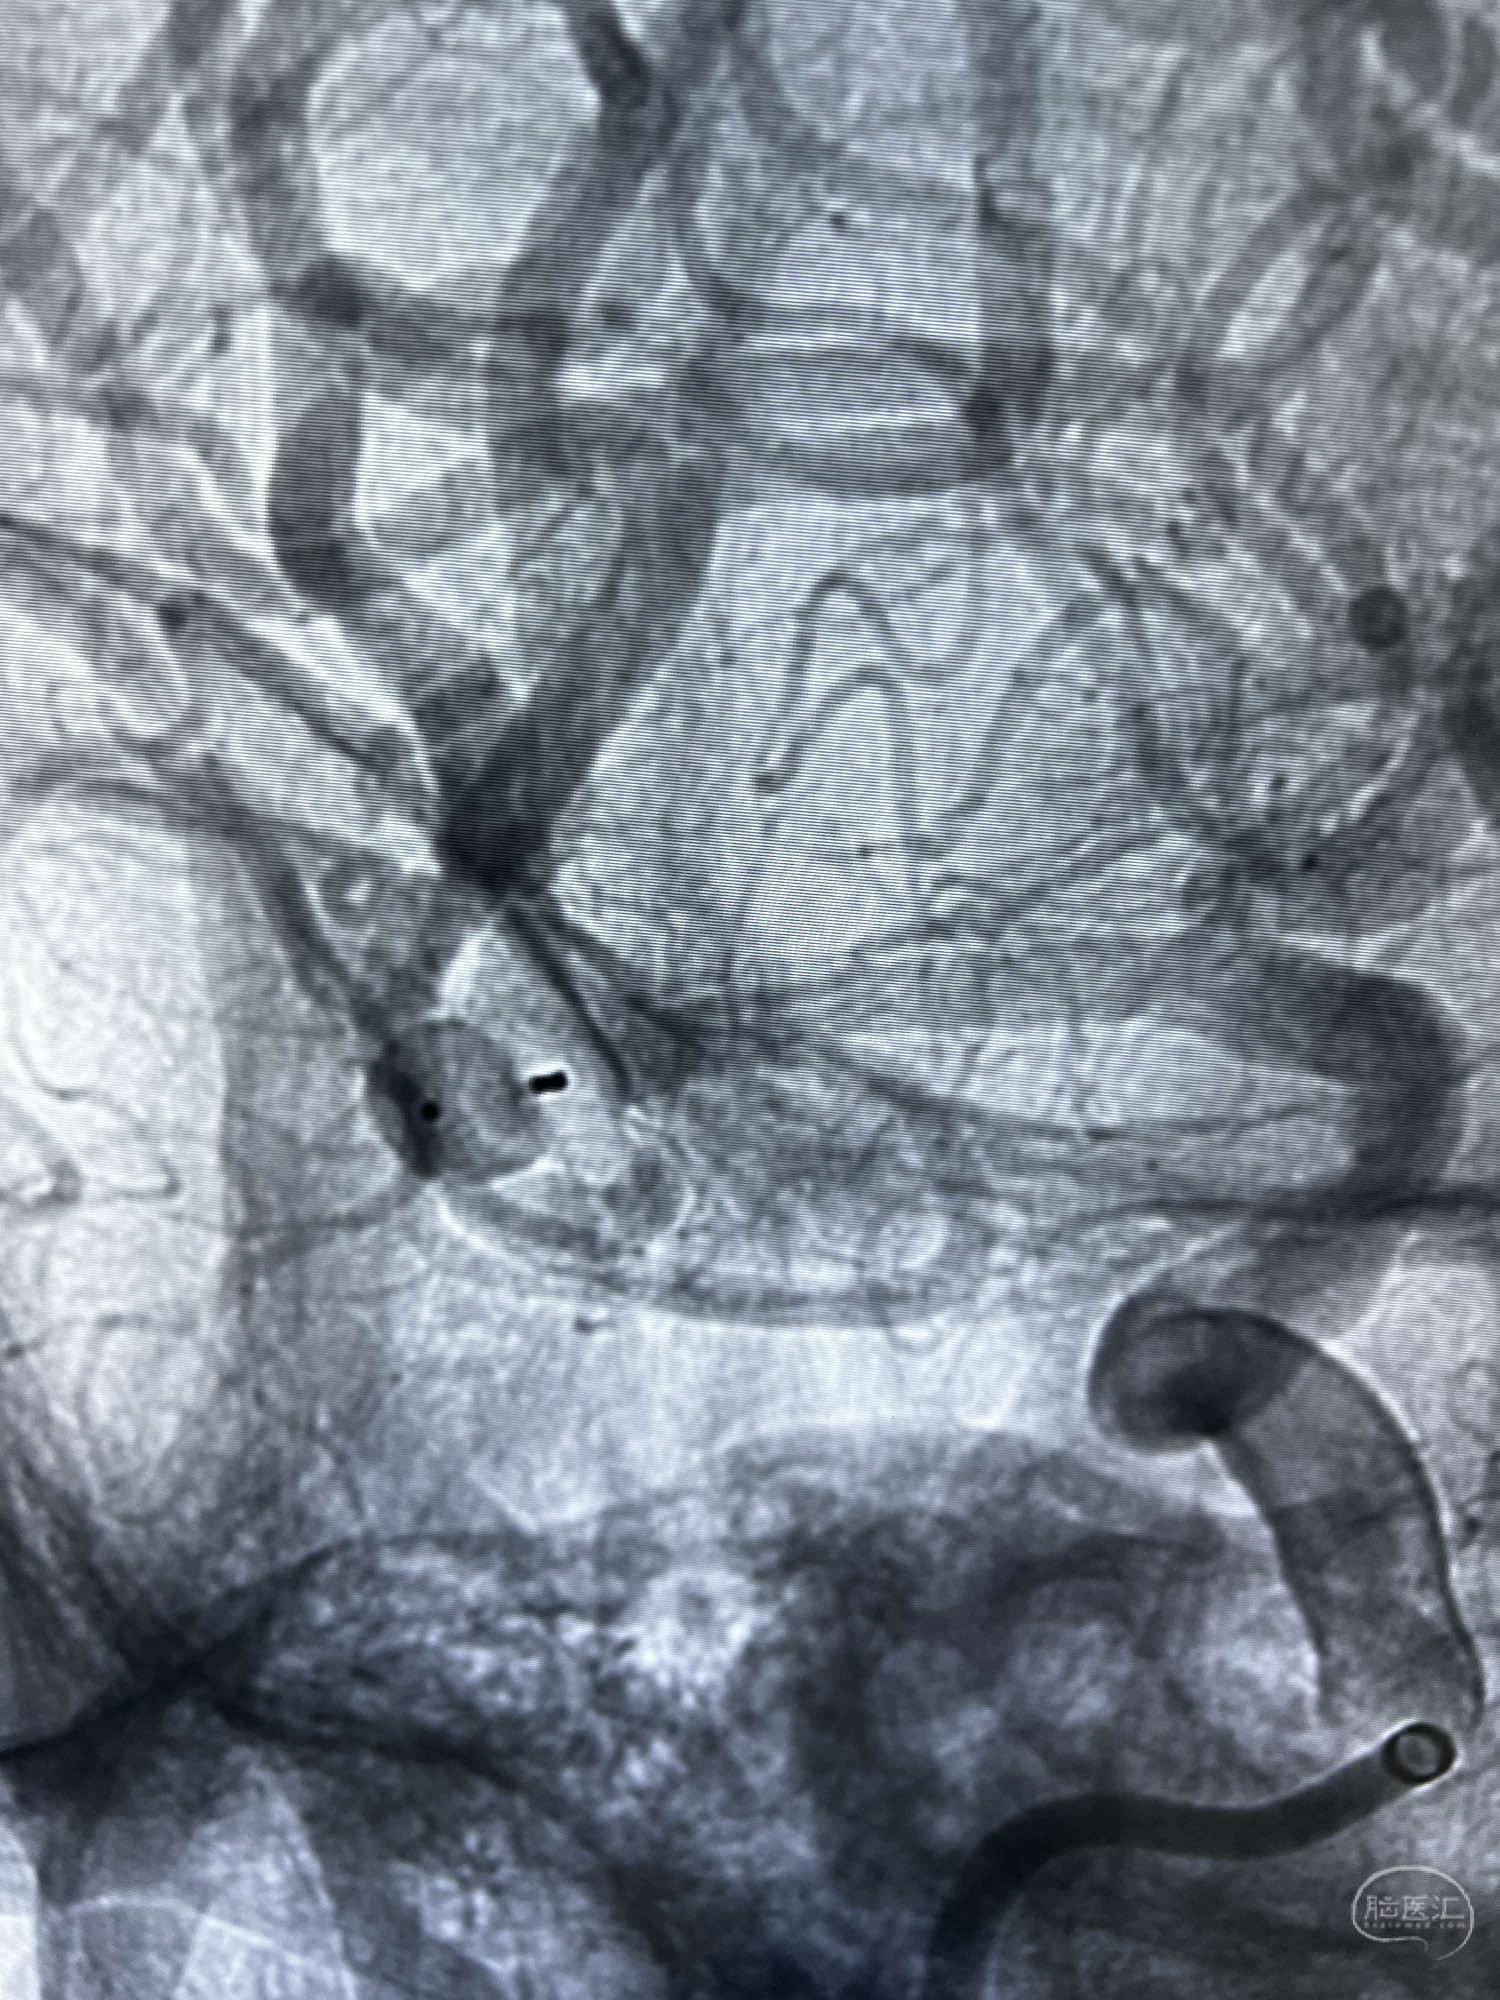

6F Neuromax➕6F115cm 心玮中间导管建立路径,sychro14微导丝➕VIA21超选至动脉瘤体内近中部,WEB5mmx3mm植入动脉瘤。

WEB瘤内扰流装置5mmx3mm经过“种子、萌芽、开花”三个阶段,打开后良好贴壁,动脉瘤内血液滞留,载瘤动脉通畅。WEB一步到位,通过瘤内扰流的方式起到栓塞动脉瘤的作用,避免了应用支架保护分支血管,简化了操作步骤,降低了术中血栓及出血的风险。